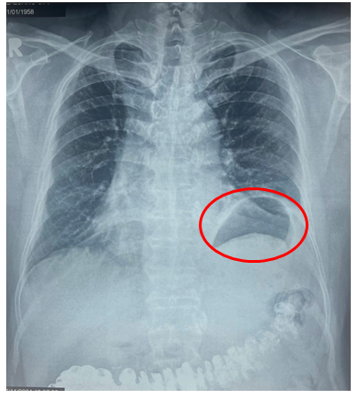

Thấy tình hình khó thở không thuyên giảm, bệnh nhân G. đến thăm khám tại Bệnh viện Bình Dân (TPHCM). Tại đây, các bác sĩ chẩn đoán bệnh nhân G. bị nhão hoành trái với hình ảnh vòm hoành trái nhô cao bất thường. Tình trạng này làm giảm thể tích lồng ngực trái, đây chính là nguyên nhân khiến ông bị khó thở khi gắng sức nhiều tháng nay mà ông không rõ nguyên nhân.

Hình ảnh vòm hoành trái cao bất thường do nhão cơ hoành trái làm giảm thể tích lồng ngực trái gây khó thở.

Để chẩn đoán bệnh nhão cơ hoành, liệt cơ hoành, các bác sĩ thường chỉ định người bệnh thực hiện chụp phim X-quang ngực và MSCT - scan ngực. Qua hình ảnh, các chuyên gia có thể thấy cơ hoành bị nâng lên cao hơn so với bình thường.